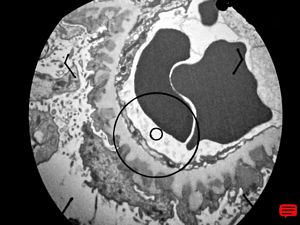

M,37y. | type I membranoproliferative glomerulonephritis (mesangiocapillary)